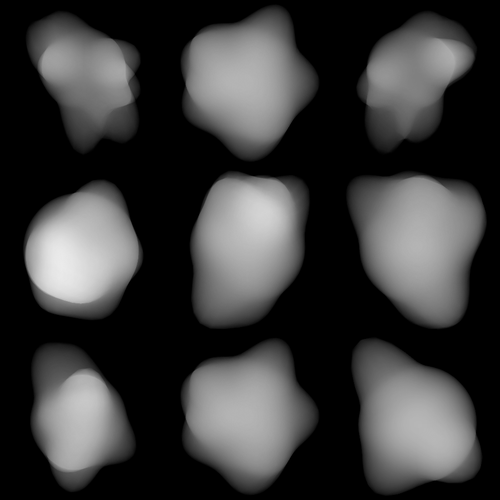

Refer to caption

(a) N=10,λ=1.5formulae-sequence𝑁10𝜆1.5N=10,\lambda=1.5

(b) N=200,λ=2.5formulae-sequence𝑁200𝜆2.5N=200,\lambda=2.5

Figure 5: Example 3D synthetic lesion masks randomly generated with different parameters.